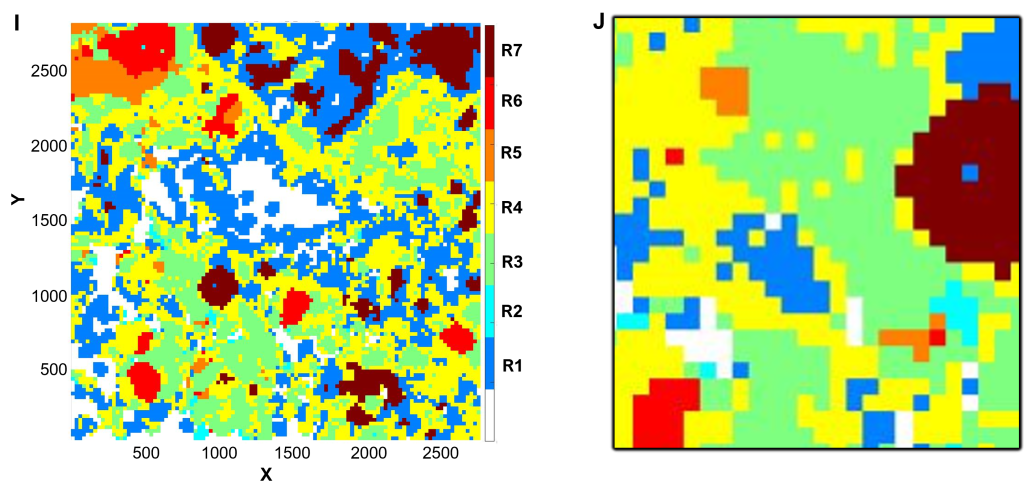

(E-H) Cell phenotyping

Cell phenotyping can be performed by gating, machine learning algorithms, or clustering (QuPath and/or CytoMAP software).

In this example, CK and CD45 expression were gated to first define epithelial (E,F) and immune cell (G,H) populations.

Utilizing selected relevant markers from the antibody panel, cell phenotypes were defined within each population by cell clustering (E-H), supervised by Dr Gonzalez Ericsson.

(E) Epithelial cell populations, color-coded as indicated in the legend.

(F) Inset of (E), corresponding to the field of view in (B).

(G) Immune cell populations, color-coded as indicated in the legend.

(H) Inset of (G), corresponding to the field of view in (B).